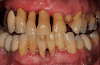

Vôi răng là những mảng bám ở xung quanh răng có màu ngà hoặc màu sậm hơn mà chúng ta có thể nhìn bằng mắt thường. Vôi răng vốn là những mảng bám thức ăn lâu ngày không được con người chú ý vệ sinh sạch sẽ, những mảng bám này sau một thời gian sẽ bị vôi hóa trở nên cứng hơn và bám chặt vào răng nên các chuyên gia gọi đó là vôi răng.

Lợi ích đầu tiên nhất mà cạo vôi răng đem lại là loại sạch các mảng bám màu vàng hoặc nâu đỏ bám trên răng và dưới nướu, giúp răng sáng bóng hơn. Khi cao răng được làm sạch, bạn tự tin hơn khi giao tiếp, cười nói. Không những thế, niềng răng thưa có đau không cạo vôi răng còn mang lại nhiều lợi ích thiết thực khác về sức khỏe.

Việc loại bỏ các mảng bám giúp phá hỏng nơi trú ngụ của vi khuẩn, ngăn chặn hiệu quả sự sinh sôi, nảy nở cũng như sự tấn công của các vi khuẩn gây bệnh, phòng chống hiệu quả các bệnh lý răng miệng như sâu răng, viêm nướu, viêm nha chu… xảy ra. Phương pháp bọc răng sứ có tốt không nếu răng thưa hở kẽ?